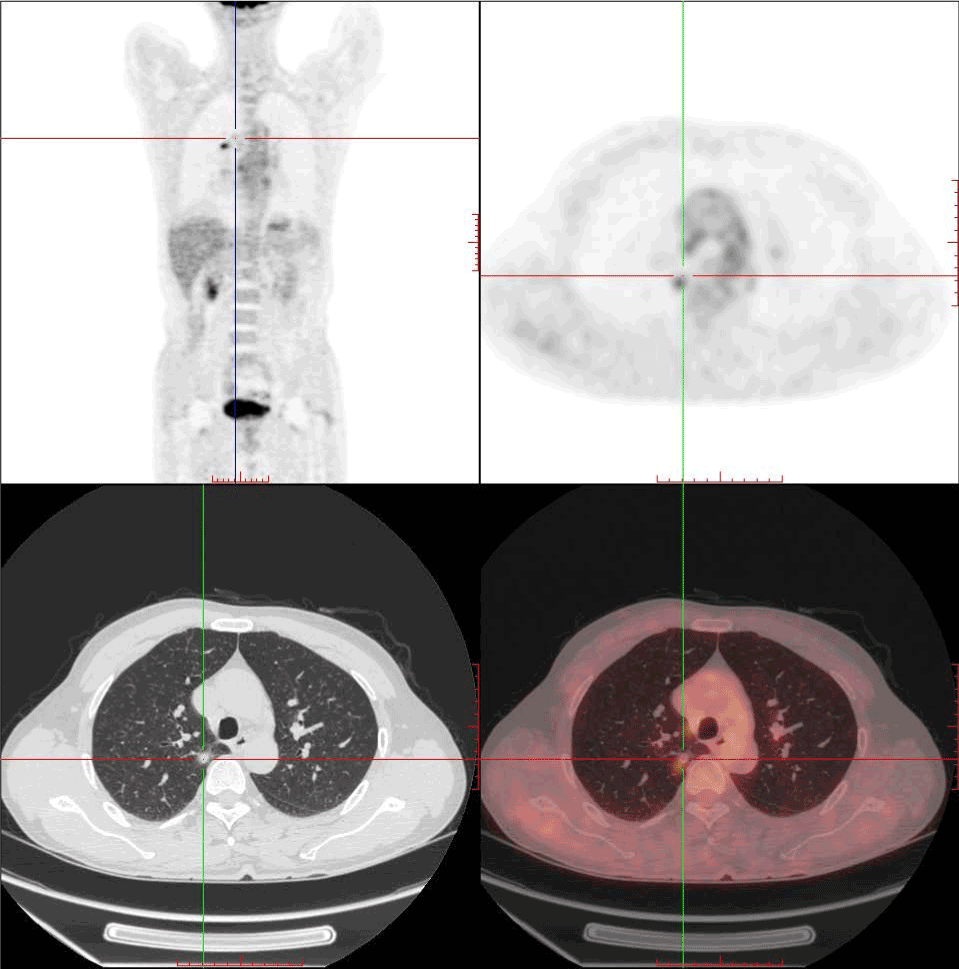

A 60-year-old Chinese man was admitted to Hospital with the history of intermittent convulsion of left upper limb with numbness of left lower limb for more than half a month, without headache, dizziness, nausea, vomiting and other symptoms. Brain magnetic resonance imaging (MRI) revealed an occupying lesion in right frontal lobe (Figure1 A-C), then brain metastasis and gliomas were considered. A chest X-ray was taken, and no abnormality was detected. Tumor markers were slightly higher and results were summarized. Subsequently, he was referred for an FDG PET/CT imaging to evaluate the whole-body, the images revealed a low-density lesion in right frontal lobe with distinct borderline, and FDG uptake was deficient completely, less than that of white matter (Figure 2). Meanwhile, a solitary pulmonary nodule was detected in upper lobe of the right lung with higher FDG uptake (standardized uptake values (SUVmax: 2.1) (Figure 3), without any other abnormality in other organs.

Figure 2. FDG PET/CT images demonstrates a focal FDG uptake deficiency in right frontal lobe, and non-contrast CT images also show a hypodense lesion at the region accordingly (35mmx34mmx18mm).

Figure 3. FDG PET/CT images show a solitary pulmonary nodule (9.8mmx12mmx11mm) in upper lobe of the right lung with focal increased hypermetabolism(SUVmax:2.1), and its edge is vague.

A larger scale study declared that NSCLC was more commonly associated with hypermetabolic rather than hypometabolic metastatic brain lesion. The PET findings of brain lesions were affected not only by the size of lesion but also by its biological characteristics [6]. One or several foci of increased 18F-FDG is highly suspicious of metastases. However, the lack of 18F-FDG uptake does not rule out metastasis, this case illustrated typically. The reason for the 18F-FDG uptake deficiency was chronic hemorrhage, which can be concluded from MR T1WI signal (brighter than brain tissue).